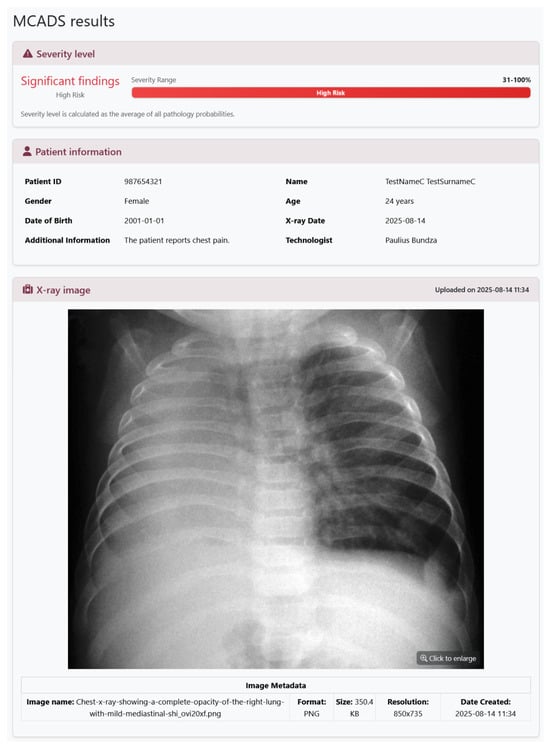

MCADS: Simultaneous Detection and Analysis of 18 Chest Radiographic Abnormalities Using Multi-Label Deep Learning

by Paulius Bundza and Justas Trinkūnas

Diagnostics 2026, 16(4), 585; https://doi.org/10.3390/diagnostics16040585 (registering DOI) - 15 Feb 2026

Background/Objectives: Chest radiography remains a fundamental diagnostic tool for evaluating thoracic disease, yet its interpretation requires considerable time and specialized expertise. Worldwide shortages of trained radiologists can lead to lengthy turnaround times and delayed treatment. This study introduces the Multi-label Chest Abnormality Detection System (MCADS), a deep-learning-driven platform designed to automatically identify and interpret 18 distinct radiographic abnormalities to address these diagnostic challenges. Methods: MCADS integrates a pre-trained DenseNet121 convolutional neural network (via TorchXRayVision) to balance broad pathology coverage with rapid inference. Images are processed asynchronously on a central server to avoid the interruption of clinical workflows. To enhance transparency and clinician confidence, the system employs Gradient-weighted Class Activation Mapping (Grad-CAM) to overlay heatmaps pinpointing image regions most influential to each predicted abnormality. The system was evaluated using eight large, publicly available datasets. Results: When evaluated on diverse datasets, MCADS achieved high area-under-the-curve performance metrics across all 18 target conditions. The platform consistently produced accurate, multi-condition analyses in under thirty seconds per image, demonstrating both reliability and speed suitable for clinical environments. Conclusions: MCADS demonstrates the potential to accelerate chest X-ray interpretation by delivering fast, reliable, and explainable multi-abnormality screening. Its deployment could reduce radiologist workload and mitigate diagnostic delays, offering a pathway to improve patient care within data-driven healthcare environments. Full article